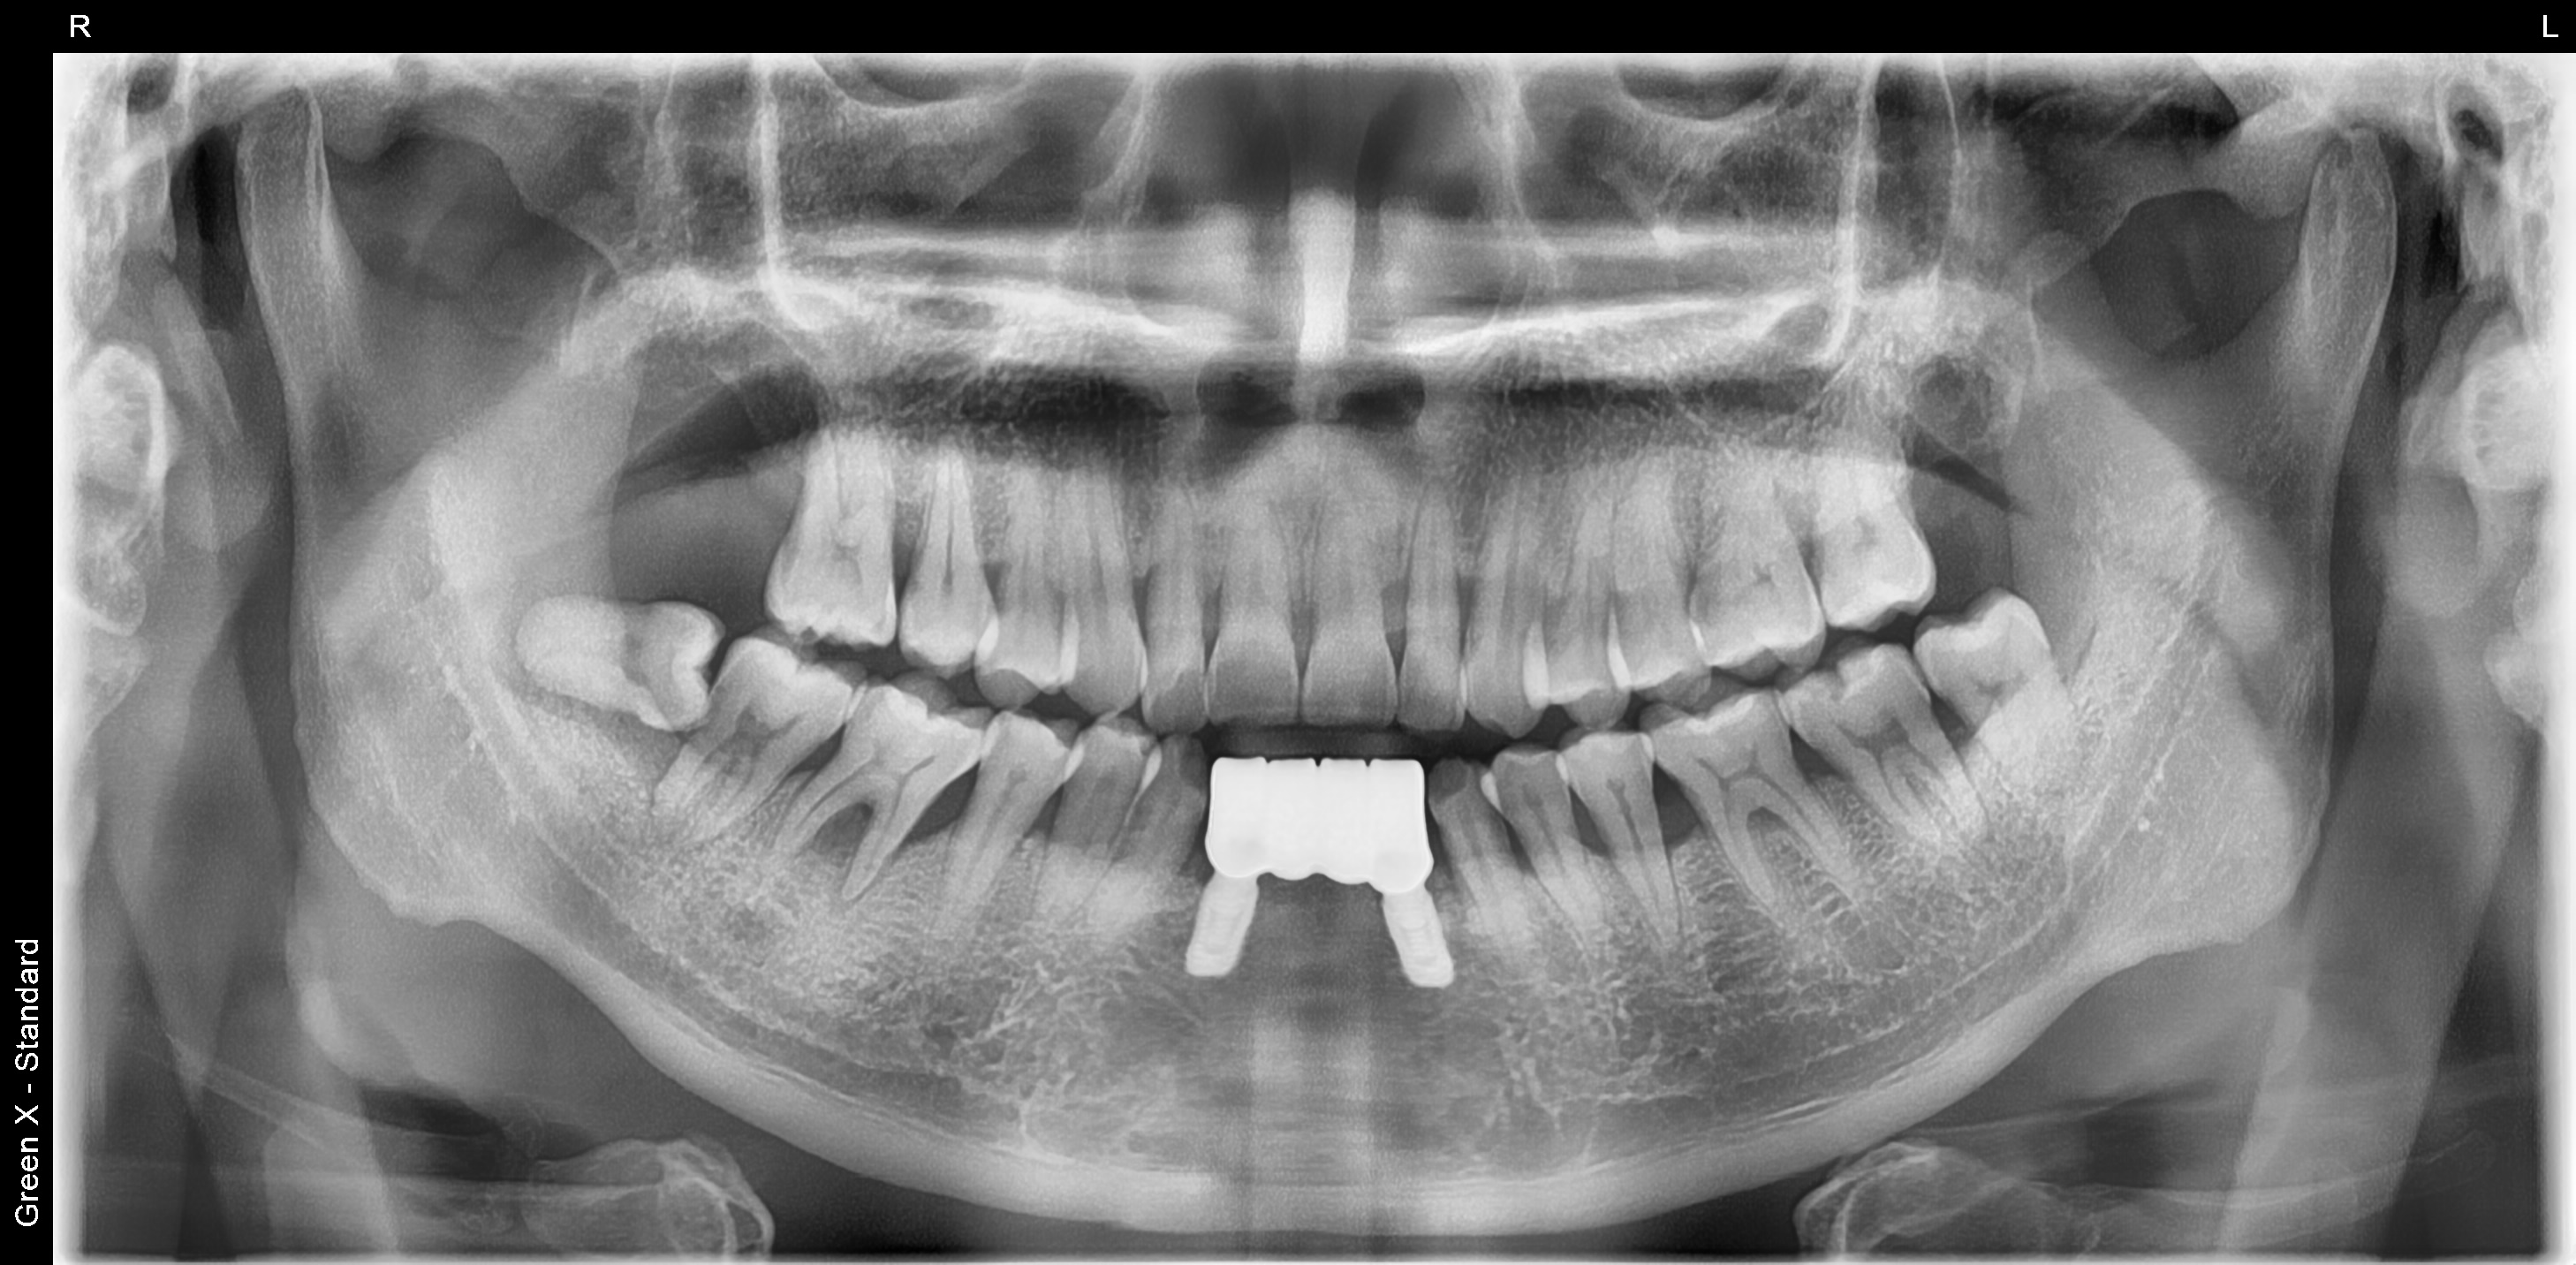

아래 앞니가 많이 흔들려서 내원하신 남성분

아래 사진을 보면 잇몸 속 치석이 아주 많고 이미 잇몸뼈가 거의다 소실되어 있습니다.

어쩔수 없이 4개의 아래 앞니를 발치 한 후 당일 2개의 임플란트를 식립했습니다.

3개월 정도 지난 후 최종 보철물을 완료해드렸습니다.